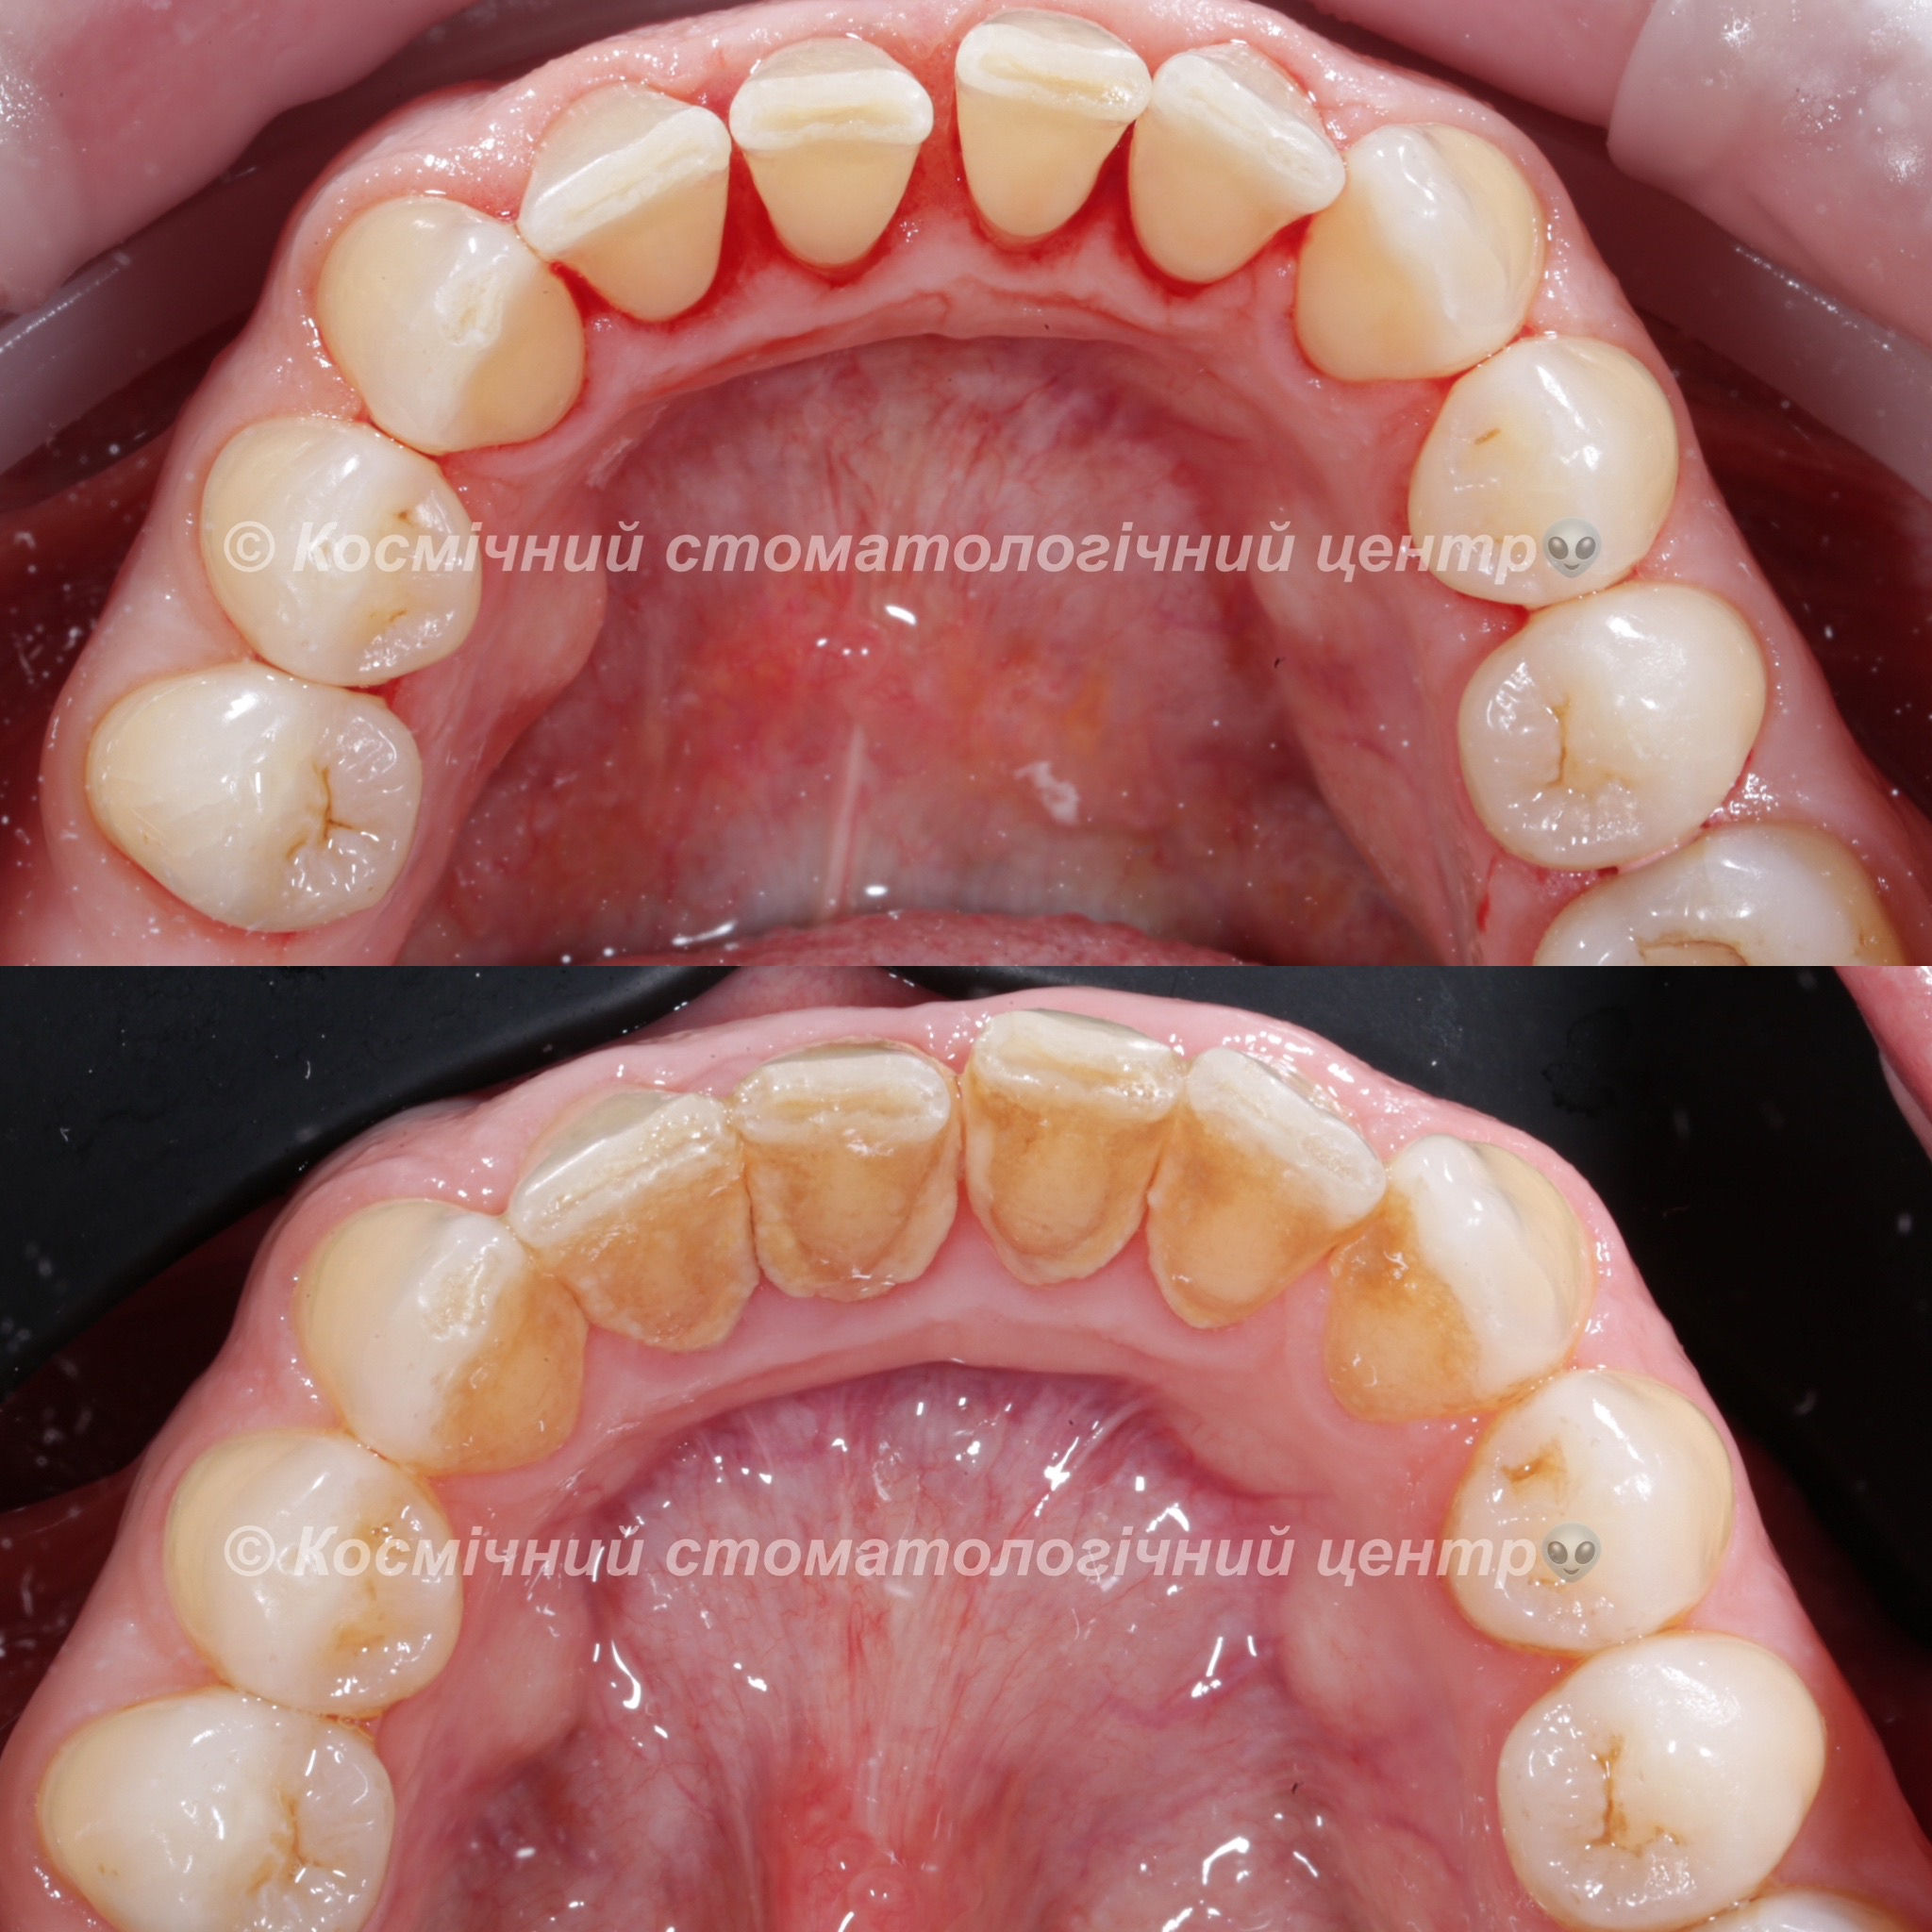

Галерея

Професійна гігієна (чистка) зубів складається з кількох етапів

Ультразвукова чистка зубів

Зубний камінь, в залежності від місця утворення, поділяється на над- та підясенний. Найбільшу небезпеку для здоров'я зубів становить другий тип, адже це дуже сприятливе середовище для шкідливих бактерій.

При проведенні професійної гігієни застосувується ультразвуковий скалер, що дозволяе видалити зубний камінь разом з хвороботворними бактеріями з підясенних кишень.

Повітряно-абразивна чистка зубів (Air Flow)

Завдяки піскоструменевому апарату з технологією Air Flow, який використовуючи тиск повітря та води, подає на зубну емаль спеціальний абразивний склад, зуби можна очистити не лише від м’якого нальоту, а й від пігменту. Для видалення нальоту, в Космічній стоматології Драганчука ми використовуємо KaVo prophy pearls supragingival calcium carbonateneutral.